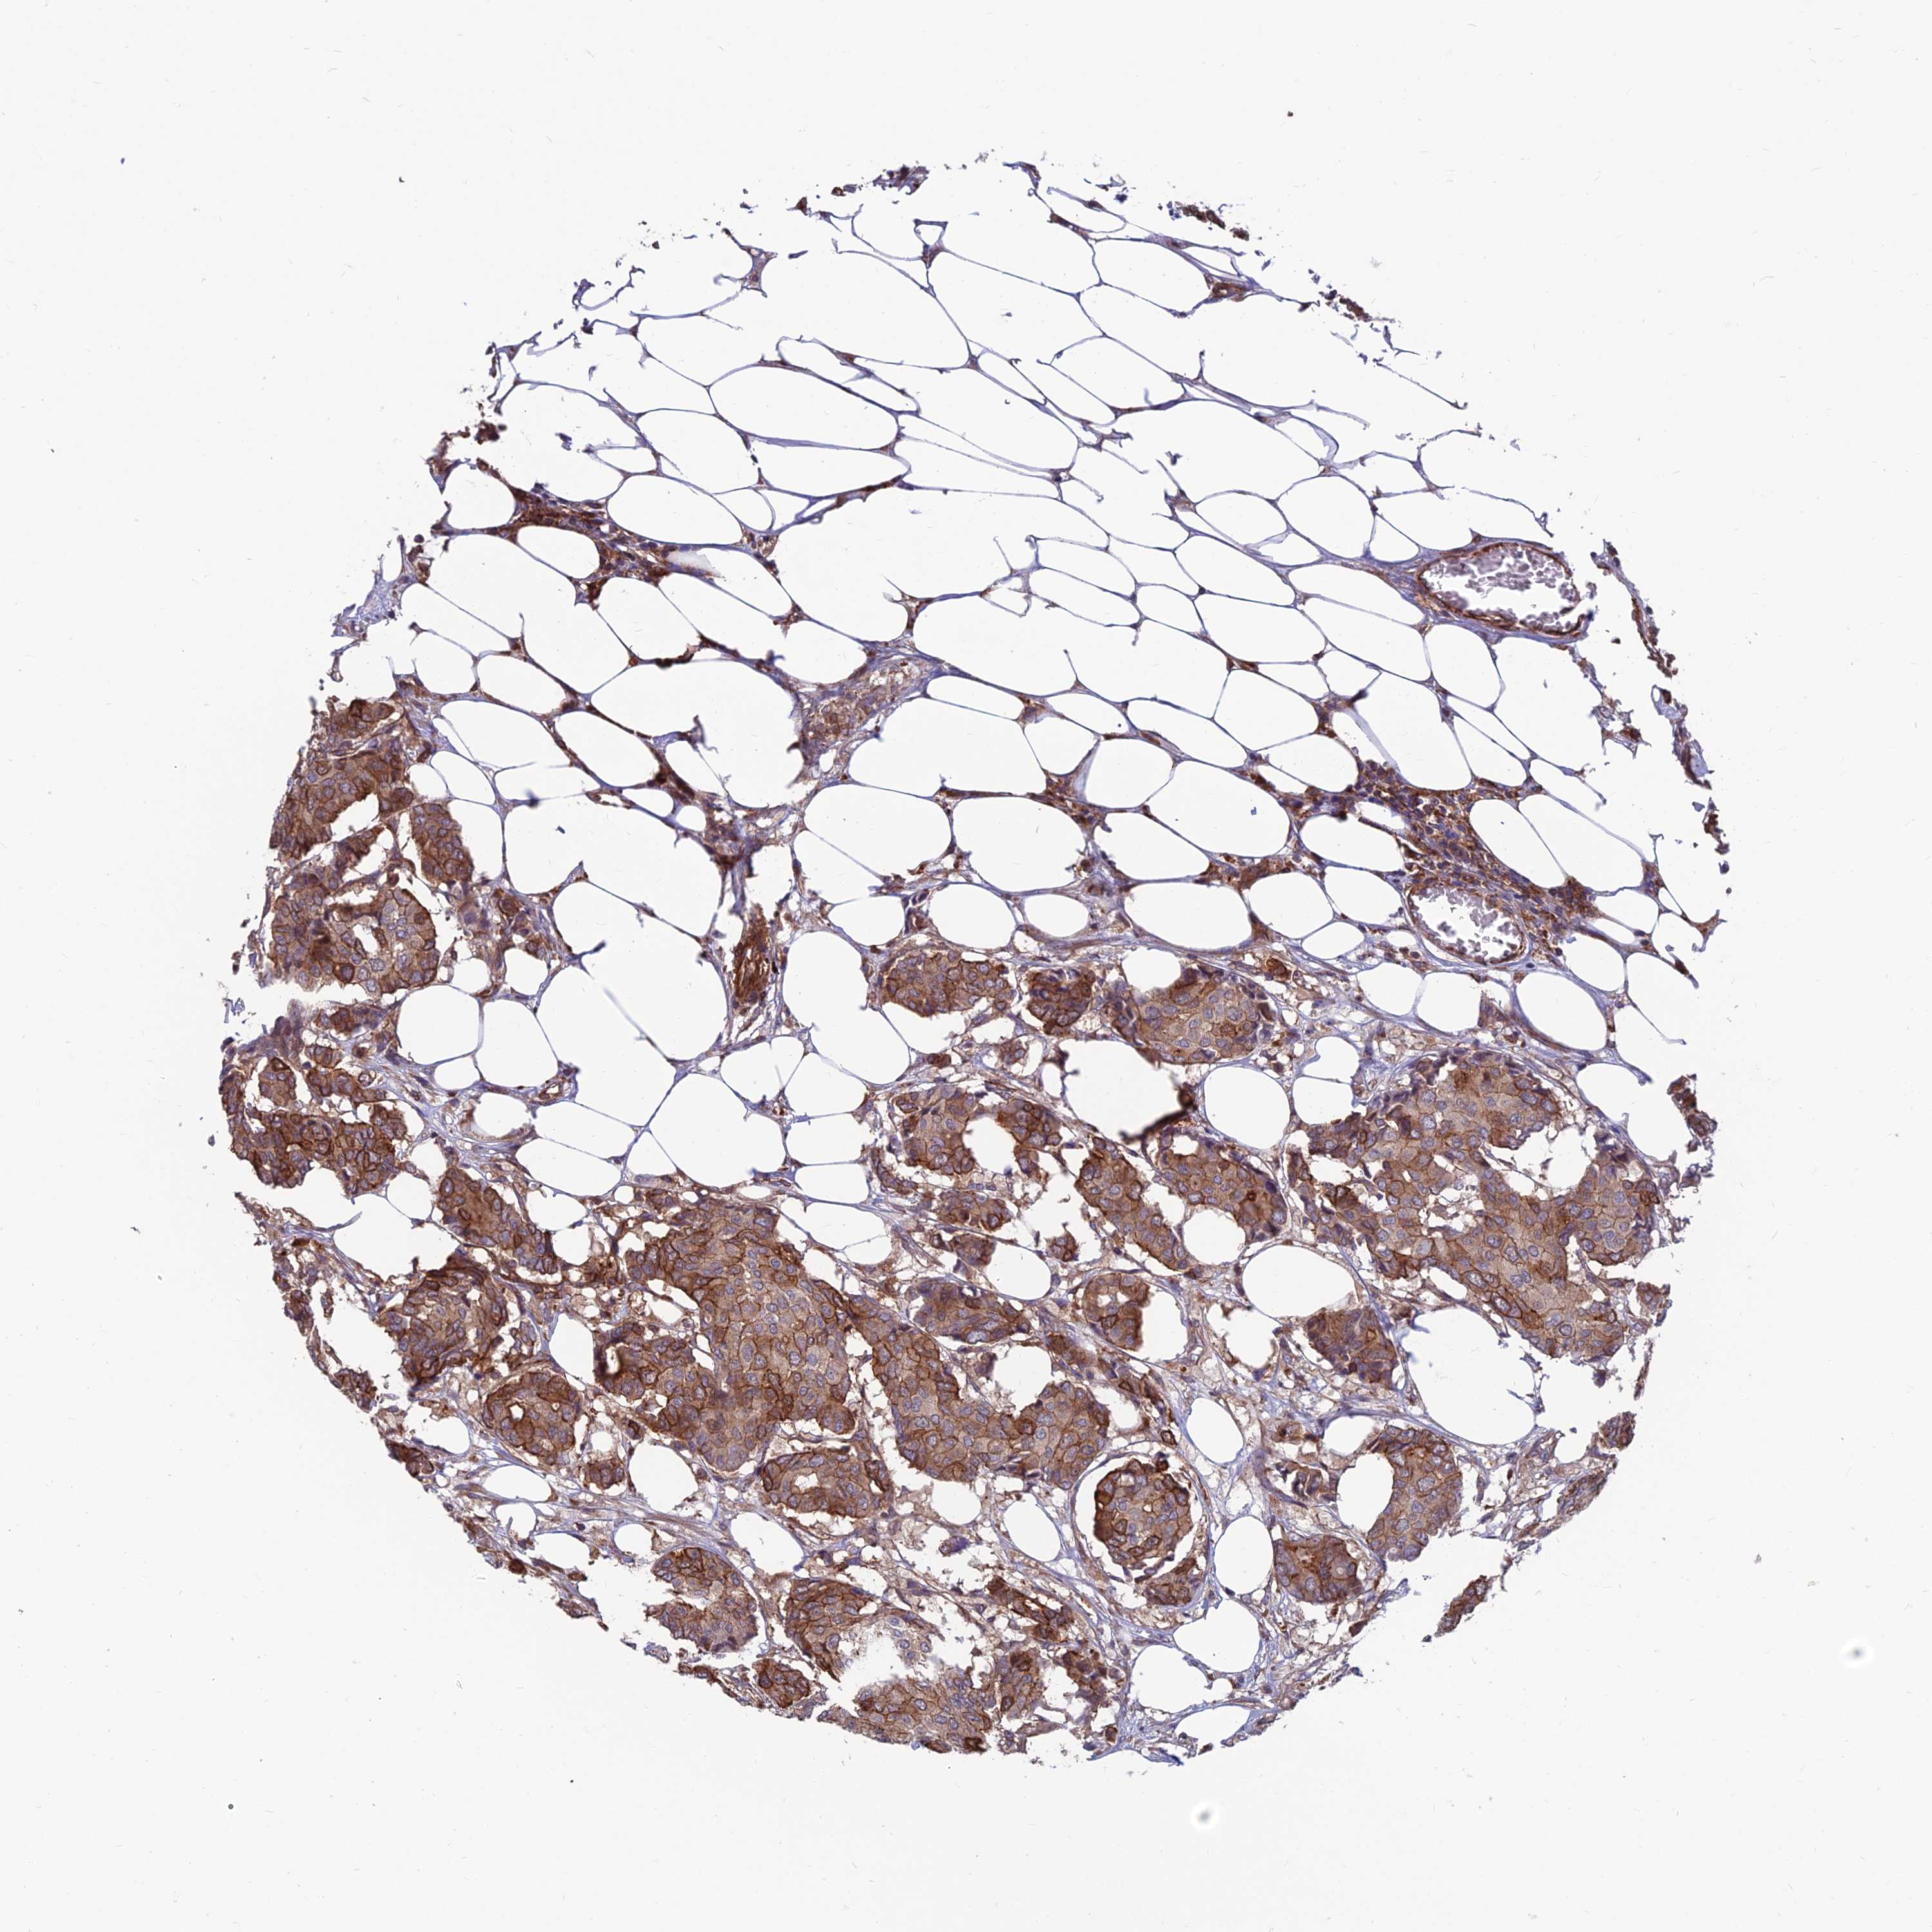

CANCER BREAST CANCER Show tissue menu

BRCA TCGA BRCA VALIDATION PROTEIN EXPRESSION